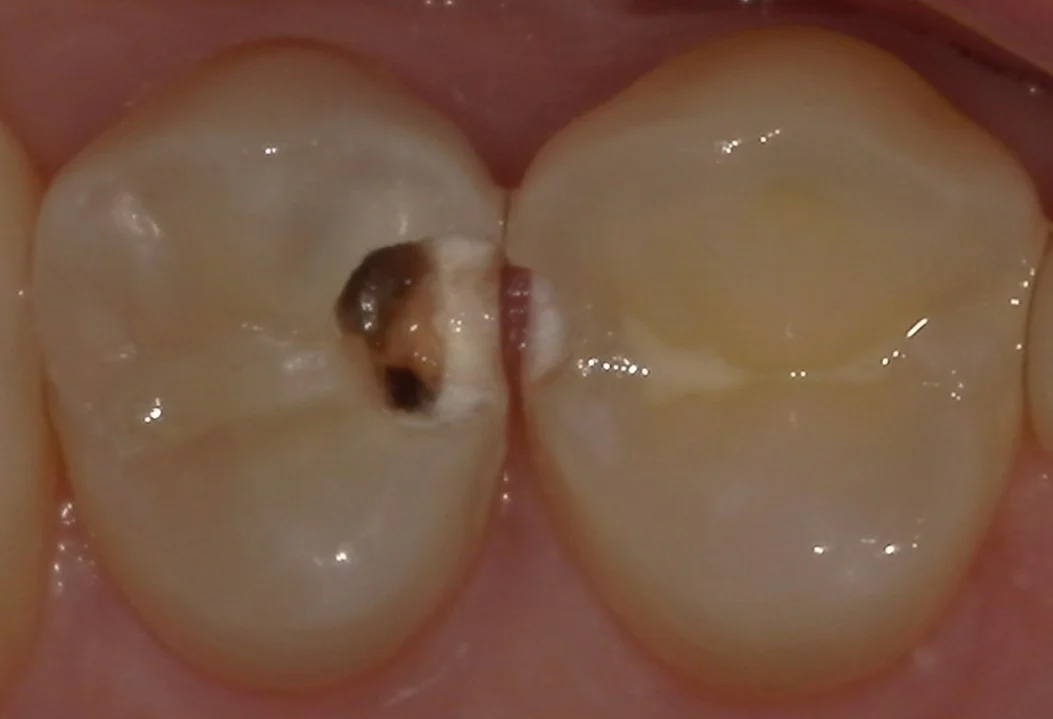

では術前の写真からです。

既に大きな穴が開いているのが分かるかと思います。

この写真の段階で、多くの歯科医療従事者の方は神経の治療を考えるレベルの虫歯です。

ご本人は痛みや沁みなどの症状は一切なかったんですが、実は虫歯って基本的に痛みを感じません。